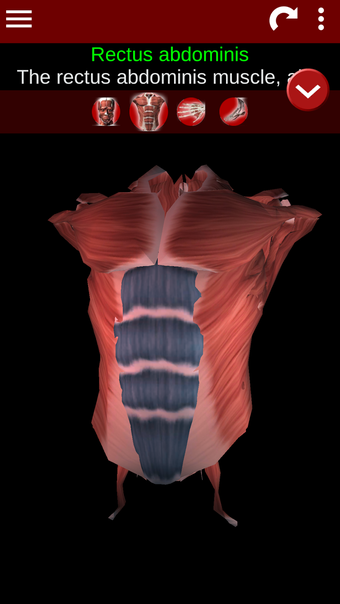

Esta herramienta educativa proporciona una descripción de cada músculo del cuerpo humano, así como un modelo tridimensional del sistema muscular. Con sólo tocar con el dedo, la aplicación revelará la información pertinente.

Los usuarios pueden hacer zoom sobre el músculo, así como elegir si ocultar o mostrar los datos. La orientación puede ser horizontal o vertical, según convenga más.